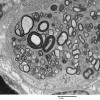

PERIPHERAL NEUROPATHY

4 AXONAL DEGENERATION

3 Electron Microscopy (3)